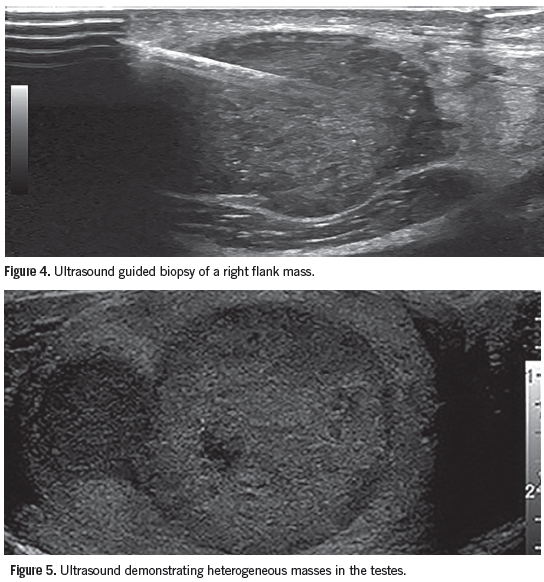

The patient was informed of the concern for metastatic disease. He was admitted for pain control, further evaluation, and management. An ultrasound-guided biopsy of the nodule on his right flank was performed (Figure 4). The oncology service evaluated the patient and diagnosed a poorly differentiated non-small cell cancer with neuroendocrine features and unknown primary source. An endoscopic retrograde cholangiopancreatography with stent placement relieved his biliary obstruction. A single treatment of radiation therapy was directed at a painful metastatic lesion on his right proximal humerus.

The patient was discharged 8 days later with a plan to initiate chemotherapy upon review of his case by the oncology tumor board. At follow-up, an elevated serum human chorionic gonadotropin level was discovered. Although the patient had no palpable testicular abnormalities, an ultrasound showed multiple masses (Figure 5). His chemotherapy was adjusted to target metastatic germ cell carcinoma of the testes.